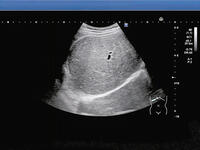

高中生送急診掃出「整塊白亮肝」 醫揭台灣人新國病 - 健康